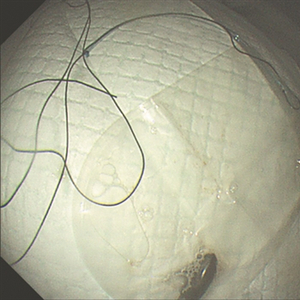

取出的橄榄状磁铁。

取出异物后,小逸慢慢清醒过来,经过半小时休息,可以正常饮水、进食。